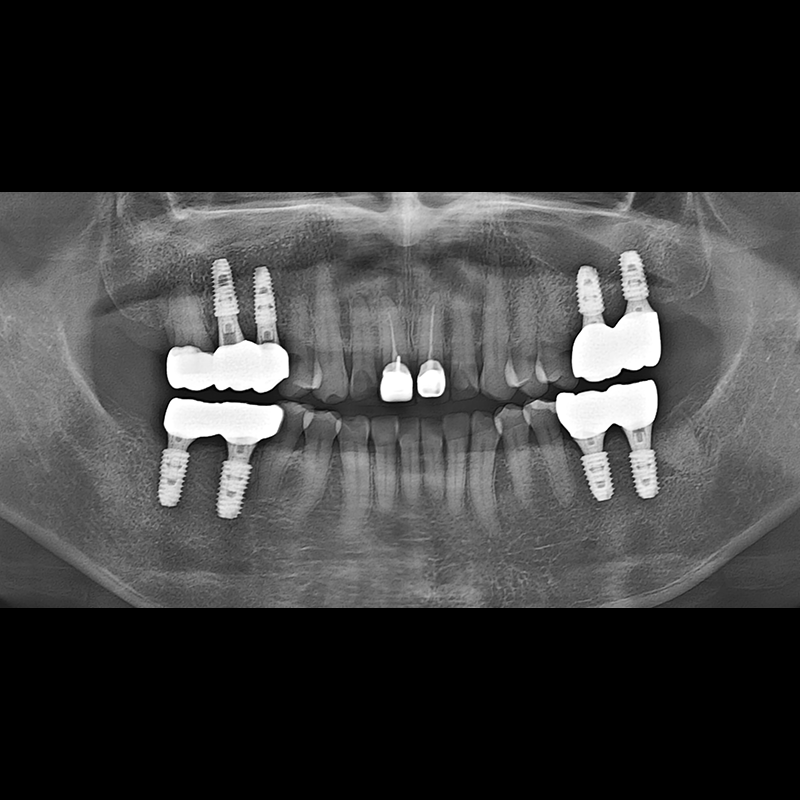

BEFORE AFTER

임플란트 전후사진 2025.05.30

결손된 치아 부분과 살리기 힘든 치아 위치에 임플란트를 식립하였습니다.